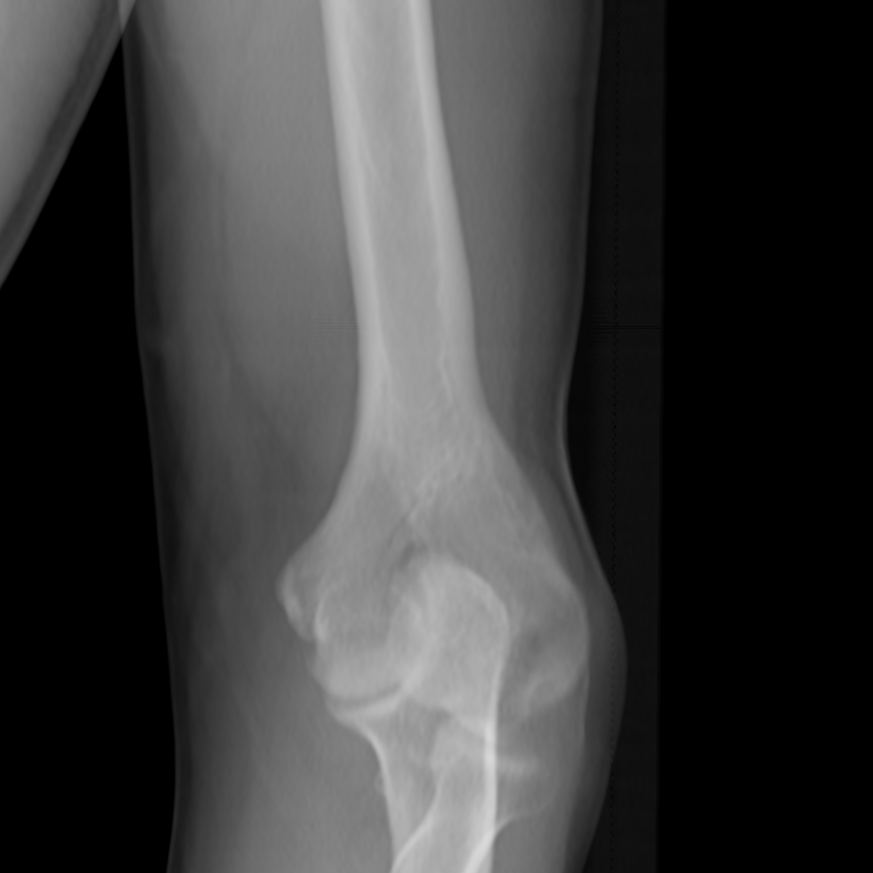

Segmenting the femur CT model into these three substructures can be performed preoperatively. However, segmenting contour pixels for each substructure intraoperatively in the X-ray images presents several challenges. The first challenge is the need for speed, as this process must be completed quickly to integrate seamlessly into standard surgical workflows. Additional challenges arise from the nature of medical imaging and the characteristics of X-ray images, such as low contrast, noise, overlapping structures, unclear or ambiguous boundaries, and artifacts. For reference, see Figure 17.

A critical step in improving the contour model predictions involved augmenting the generated DRRs at various stages to closely resemble real X-ray images. The DRRs were generated using 3D Slicer [29, 30], a robust and open-source toolbox for medical imaging. Unlike real X-ray images, which exhibit significant noise and visual artifacts (see Figure 18), the generated DRRs are typically very clean and artifact-free (see Figure 17). To bridge this gap, our data augmentation strategy focused on introducing various levels of Gaussian noise, random contrast adjustments, applying small random rotations, and simulating white edge artifacts. These standard techniques have been shown to effectively bridge the imaging domain gap between synthetic and real-world data, as supported by prior work [31]. Despite these domain gaps, our study demonstrates that our model, trained exclusively on synthetic data, generalizes exceptionally well to real X-ray images. This claim is supported by Figures 3, 4, and 5 of the main article which show results obtained on real X-ray images.